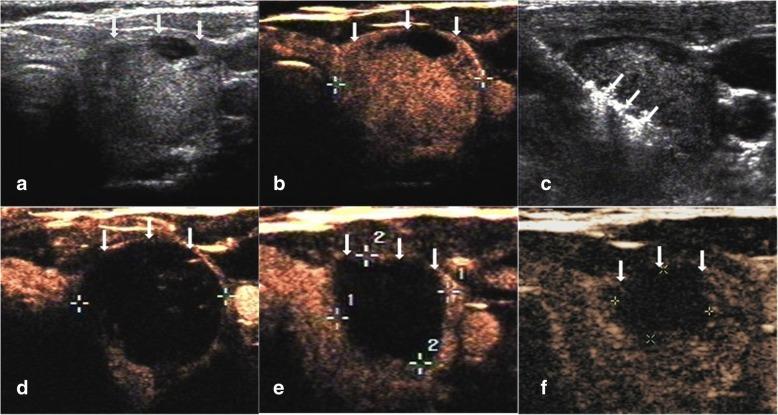

This retrospective study evaluated 194 non-functioning solid benign TNs of 103 patients. The TNs were categorized as small (≤5 ml), medium (5.1 to 13 ml), intermediate (13.1 to 30 ml) and large (over 30 ml) according to the initial volume of TNs before ablation. Clinical evaluation and contrast-enhanced ultrasound (CEUS) were carried out before ablation and the follow up at 1, 3, 6 months and every 6 months after ablation. All patients were asked to assess the cosmetic score (1-4 scores) and symptom score (0-10 scores) before ablation and every follow up after ablation.

All patients underwent RFA without any major complications. The mean treatment sessions were 1.5 ± 0.6. 98 nodules required a single session (98/194, 50.5%), 87 required two sessions (87/194, 44.9%), 9 required three sessions (9/194, 4.6%). The average follow up months were 16.3 ± 5.6 (range, 6-24 months) and no nodule regrew in our study. After RFA treatment, the TNs volume significantly decreased (P < 0.001). The small group of nodules shrunk larger compared to the medium, intermediate and large groups (P < 0.001). Cosmetic signs and pressure symptoms were significantly improved, particularly in the intermediate and large groups (P < 0.05).

方法

所有患者均顺利完成 RFA 治疗,无重大并发症。平均治疗次数为 1.5±0.6 次。98 个结节(98/194,50.5%)需单次治疗,87 个结节(87/194,44.9%)需 2 次治疗,9 个结节(9/194,4.6%)需 3 次治疗。平均随访时间为 16.3±5.6 个月(6-24 个月),研究期间无结节复发。RFA 治疗后,TN 体积明显缩小(P<0.001)。与中、大组相比,小组结节的缩小更为明显(P<0.001)。美容体征和压迫症状显著改善,尤其是中、大型结节(P<0.05)。